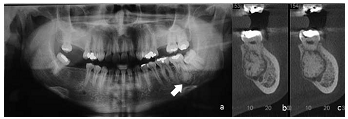

Homem de vinte e cinco anos de idade, melanoderma, compareceu a unidade odontológica para a remoção de terceiro molar superior. Por imagem radiográfica, constatou-se aumento de volume radiopaco fundido ao ápice do dente 37 circundado por um fino halo radiolúcido, conforme indicado pela seta na imagem radiográfica a. Foi solicitada a realização de tomografia, para confirmação das características previamente identificadas. As imagens da tomografia correspondem às indicadas pelas letras b e c.

Considerando-se o aspecto patognomônico da lesão, é correto afirmar que se trata de